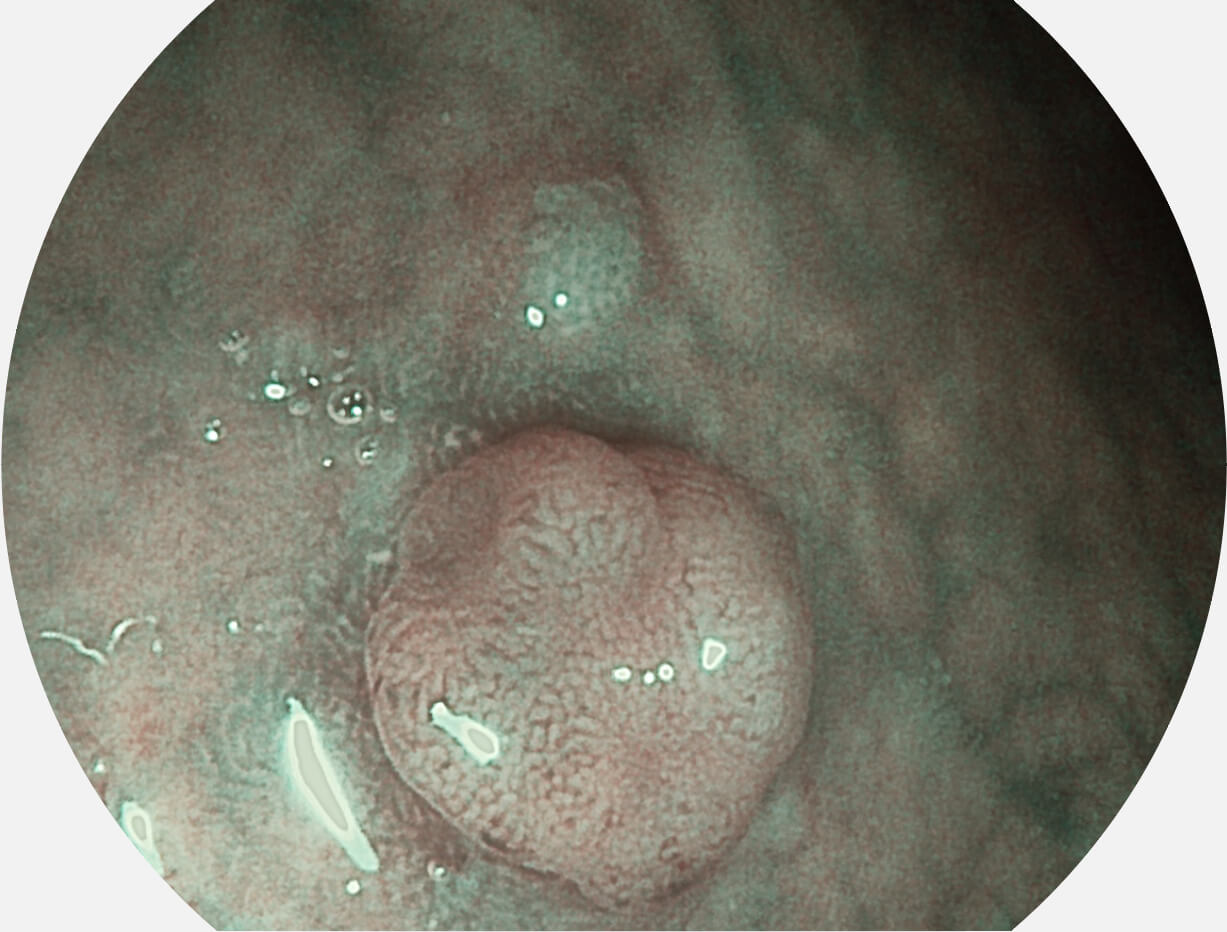

光电复合染色成像技术

Versatile Intelligent Staining Technology, VIST

强调浅层黏膜结构的同时,保证照明亮度和提升浅层微血管与中层血管颜色对比度,病变边界更清晰。

• 白光图像 VIST图像